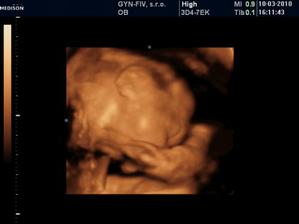

Ako rýchlo rastieme v brušinku 🙂

tatianka ďakujeme veľmi pekne 🙂 aj my sa z nich vytešujeme, kým je malinká v brušku a nevidím ju naživo